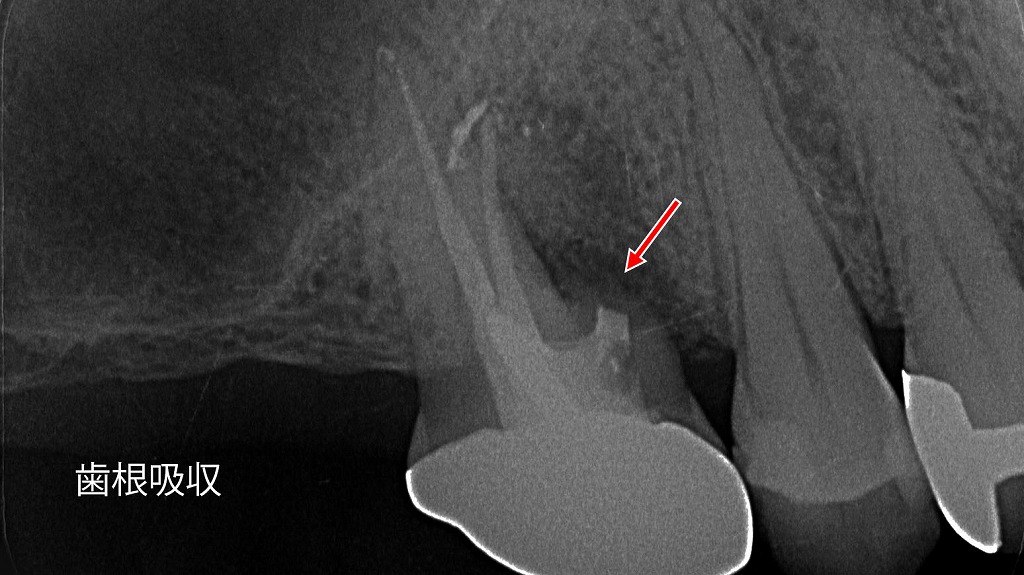

5. その他の動揺歯

- 概要: 加齢や咬合力の異常、歯根吸収などにより歯が動揺している状態。

- 適用理由: 動揺を抑えることで、歯や周囲組織へのさらなる負担を軽減します。